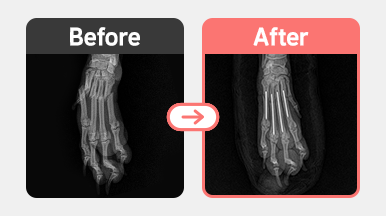

[골절 수술] 말티푸 / 1살 / 중수골 골절 / 수내정 삽입 고정

진단명 : 전지 중수골(Metacarpal Bone) 골절

치료내용 : 골절 정복 및 수내정(intramedullary pin) 삽입 고정술 진행

신체 촉진 및 방사선 촬영 결과, 전지 중수골(Metacarpal Bone) 골절이 확인되었습니다.

아이의 체중과 뼈의 정렬 상태를 고려해 수내정(Intramedullary Pin) 삽입을 통한 내부 고정술을 진행하였습니다.

수술은 정복 위치를 정확히 맞춘 뒤 골수강 내로 금속 핀을 삽입하여 고정하였고,

현재는 보행 시 통증 반응이 감소하고 있으며, 핀 고정 상태도 안정적으로 유지되고 있습니다.